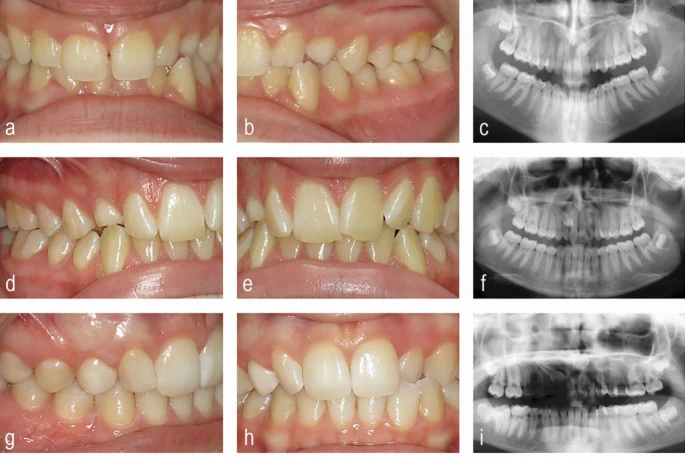

Врачу-стоматологу общей практики (ВСОП) важно не успокаиваться мыслью о том, что у подростков с устойчивыми молочными клыками верхней челюсти (Рис. 2) происходит нормальное (хотя и медленное) dentalное развитие. Это впечатление может усугубляться, когда молочные вторые моляры все еще присутствуют, а аномалия прикуса кажется незначительной. Стоматологическое развитие значительно варьируется в зависимости от хронологического возраста, и наличие молочных моляров не является причиной откладывать обследование по поводу непрощупываемого постоянного верхнего клыка у подростков.

Превентивное ведение небно дистопированного верхнего клыка

Раннее выявление аномального положения верхнего постоянного клыка и iniciрование превентивного лечения для стимуляции его самокоррекции может быть полезным по нескольким причинам. К ним относятся: избежание необходимости будущего хирургического обнажения и ортодонтического вытяжения, снижение риска резорбции корней соседних верхних резцов и избежание потенциально prolongedленного ортодонтического лечения. Однако доказательная база неоднозначна, не самого высокого качества и трудна для интерпретации. Превентивное лечение при НДВК в основном основано на принципе наличия места в этой области верхнечелюстной дуги, что может включать только удаление сохранившегося молочного клыка (Рис. 3) или удаление этого зуба в сочетании с ортодонтической механикой для расширения или удлинения зубной дуги.